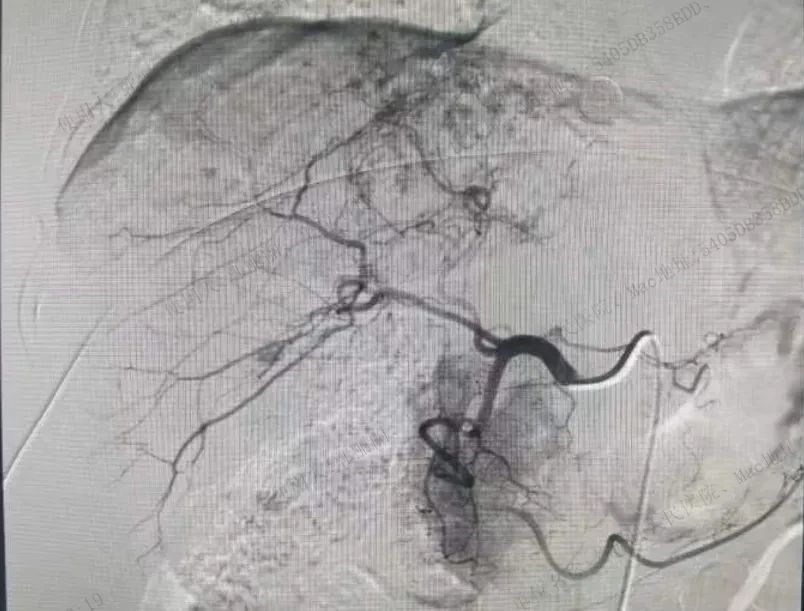

手术由副院长、心脑血管专家李尧亲自挂帅,并得到了援疆介入专家徐兰彬医生以及内科曹战江医生的全力支持。在充分评估了患者的病情和手术风险后,医疗团队决定采用腹股沟区股动脉穿刺介入的方式进行手术。这种手术方式具有创伤小、恢复快的优点,能够最大程度地减轻患者的痛苦和术后恢复时间。

手术过程中,徐兰彬医生凭借其丰富的临床经验和精湛的技术水平,成功地为丁女士实施了股动脉穿刺肝脏血管瘤栓塞术。整个手术过程历时1.5小时,患者生命体征平稳,未出现任何并发症。术后,丁女士恢复迅速,很快就能够下床活动,这让她和家人都感到非常高兴和满意。